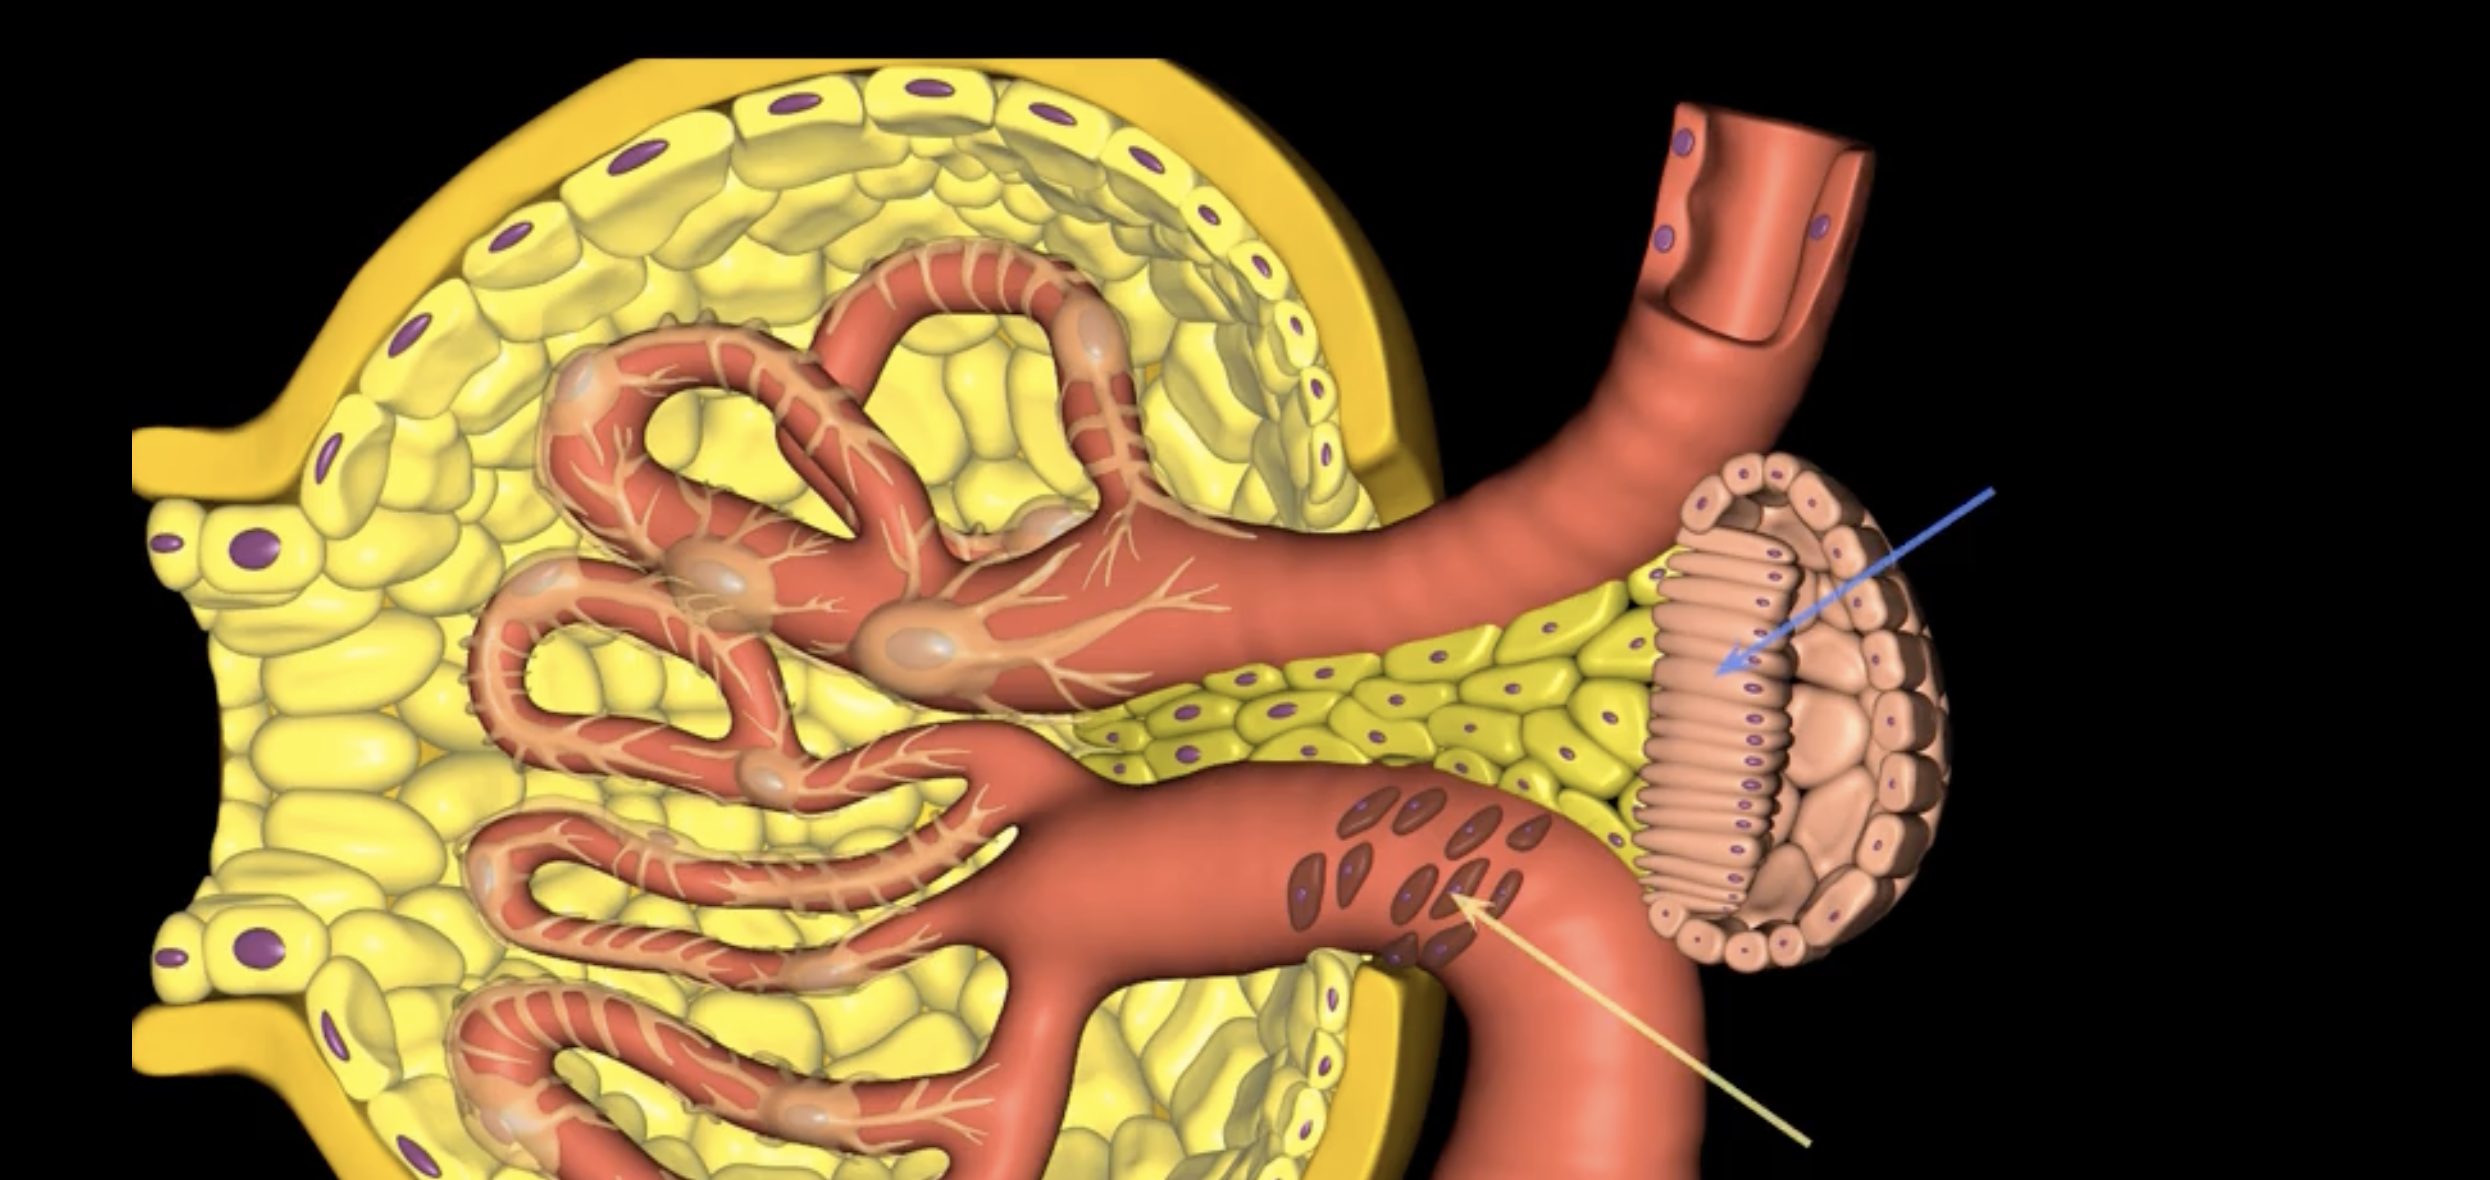

afferent arteriole

yellow

glomerulus

green

efferent arteriole

purple

orange: peritubular capillaries

green: vasa recta

efferent arteriole give rise to orange and green